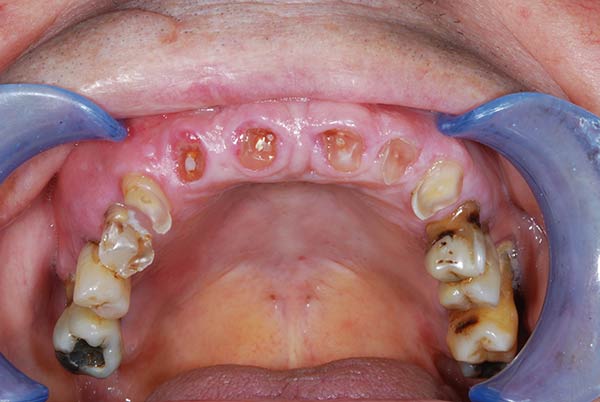

Con protesi fissa superiore e protesi fissa inferiore

I denti irrecuperabili dell'arcata superiore ed inferiore del paziente di anni 65 sono stati sostituiti da 10 impianti, cioè protesi radicolari endo-ossee che sostengono le protesi fisse superiore ed inferiore.